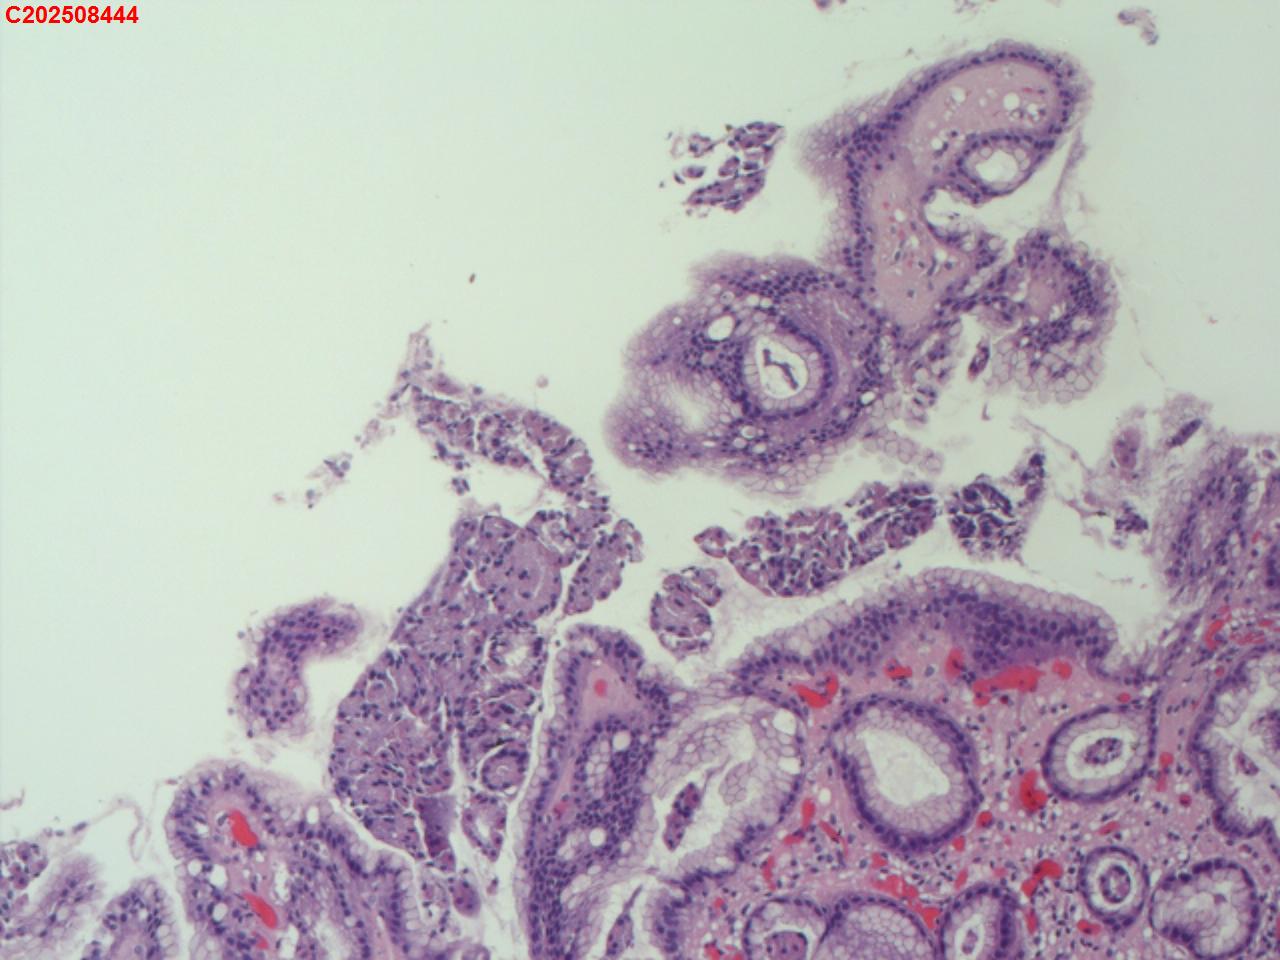

胃体可见多发直径2mm息肉,稍隆起,圆丘形

图3

增生性息肉

符合增生性息肉。